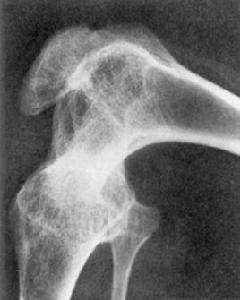

關節強直分為骨性與纖維性。骨性強直是關節明顯破壞後,關節骨端由骨組織所連線。X線表現為關節間隙明顯變窄或消失,並有骨小梁連線兩側骨端。多見於急性化膿性關節炎癒合後。

系原發性或繼發性關節軟骨退行性改變。關節軟骨磨損,關節間隙變窄,軟骨下骨質硬化,關節邊緣骨贅形成。原發性病變發生於50歲以後,女略多於男,多關節受累,以...